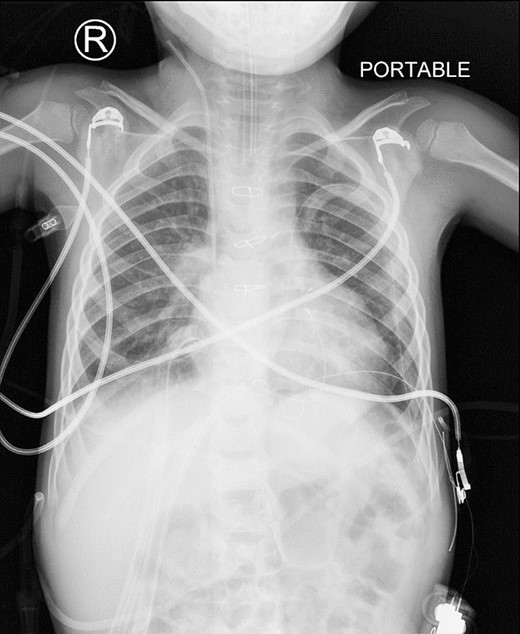

Post-surgery, the patient was transferred to the Pediatric Cardiac Intensive Care Unit in stable condition. Follow-up chest X-rays confirmed successful repair of the diaphragmatic hernia (Fig. 3). However, 3 weeks later, the patient developed intermittent complete heart block. An electrophysiological assessment confirmed the need for a pacemaker, and a VVI pacemaker was implanted in the left epigastric area. The procedure involved creating a pocket under the left rectus muscle, entering the pericardium through the left chest, and implanting a bipolar electrode tunneled to the pocket. The pacemaker was successfully connected and placed, showing favorable threshold and impedance values.

This is a postoperative AP view of chest X-ray showing the disappearance of the abnormal mediastinal lucency representing loops of bowel.